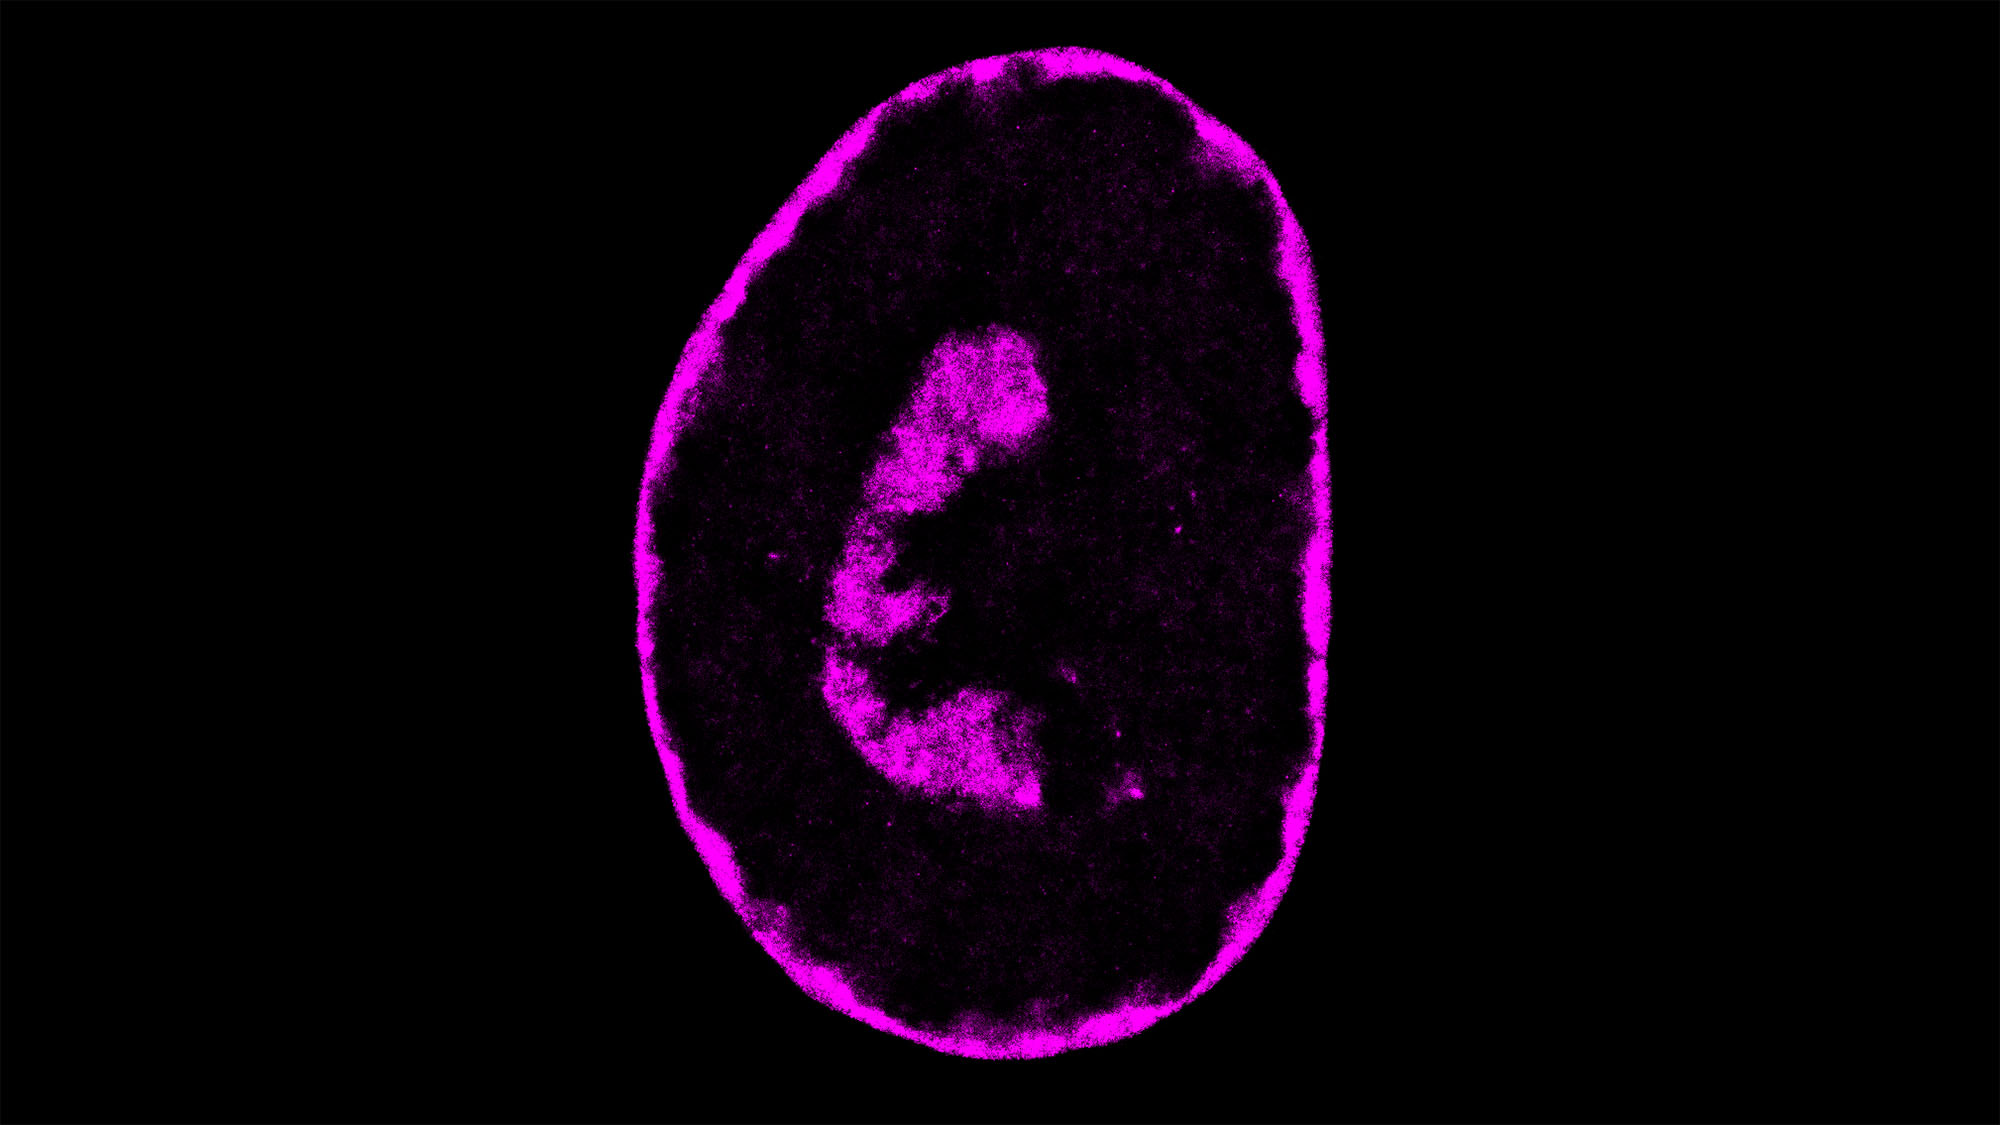

A la imatge s’observa com el genoma humà està compactat dins de la cèl·lula després d’haver estat infectada amb el virus de l’herpes. Una figura que s’ha pogut obtenir gràcies a la combinació de microscòpia de superresolució que permet observar estructures de fins a 20 nanòmetres i Hi-C, una tècnica que mostra els fragments d’ADN que es toquen dins del nucli.